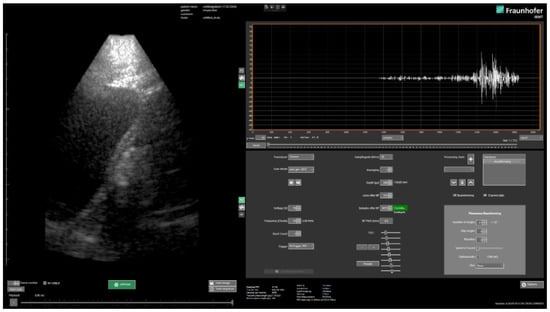

2.3. Beamforming and Software

Image reconstruction is performed in real-time using a GPU (OpenCL, Khronos Group, Beaverton, OR, USA)-based implementation of plane wave compounding [15] approach in the in-house developed clinical style user interface USPilot (Figure 3). Other reconstruction methods can easily be implemented via an SDK. The number of plane wave angles, as well as the increment can be freely selected by the user. Other transmit parameters such as the frequency, the burst count or the voltage can be adjusted as well. On the receive side, the data sampling rate, averaging factor and TGC can be selected.

The reconstruction can be adjusted in terms of the size and resolution of the reconstruction grid (lateral and axial pixel/sample count), the speed of sound and apodization. Furthermore, customized algorithms (e.g., bandpass filtering or alternative beamforming approaches) can be inserted into the (real-time) reconstruction pipeline. The software allows the visualization of reconstructed (compounded) B-scan images as well as the pre-beamformed channel data (in time or frequency) domain, which makes it ideal not only for clinical research, but also for educational purposes or research on reconstruction algorithms. In addition to controlling the system via the USPilot, an open programming interface (C#/C++/Matlab with SDK) is made available, which provides access to the same transmit, receive and beamforming parameters as in the case of the UI. A custom but open binary data format (*.orb) is chosen for storage of the pre-beamformed and reconstructed ultrasound data. Meta-data such as transmit and receive parameters are stored with the actual ultrasound data by default and import tools for Matlab/Python/C/C++ are made available.

Figure 3. Clinical style user interface USPilot.